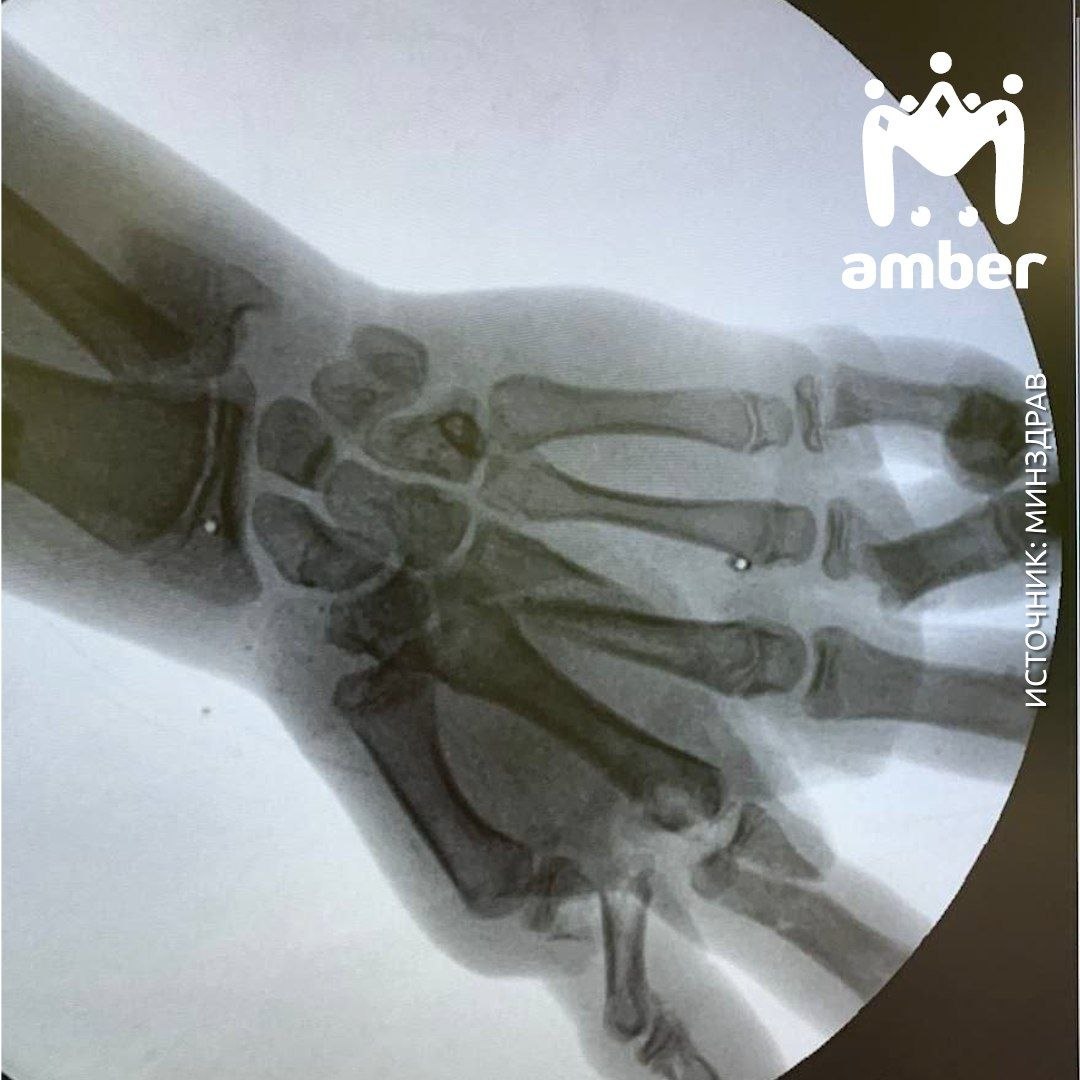

13-летний пацан нашёл старый снаряд во дворе дома. Дальше: гениальная идея, взрыв, шок и машина скорой помощи. Врачи поставили ему перелом левого предплечья со смещением, раны на левой голени, лбу и перелом левой кисти с кровотечением.

Мальчик мог остаться без руки, но врачи ДОБ собрали её из обломков. Восстанавливаться окончательно он будет не меньше шести месяцев.